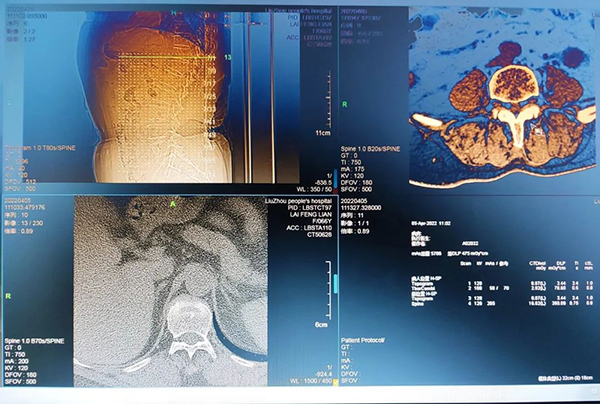

在柳州市人民醫院緊密型醫聯體的大力幫助和支持下,沙塘鎮中心衛生院這臺CT機4月份正式開機運行,提供24小時門、急診CT檢查服務。該CT機性能先進,功能齊全,分辨率高,圖像清晰并且處理速度快。

沙塘鎮中心衛生院CT采用遠程診療,即患者在沙塘分院做CT檢查,報告由柳州市人民醫院放射科專科醫師發布。同時沙塘分院也是柳州市人民醫院醫學影像科遠程會診成員單位,對疑難雜癥可實現遠程會診,市內頂級專家攜手為您的健康保駕護航!